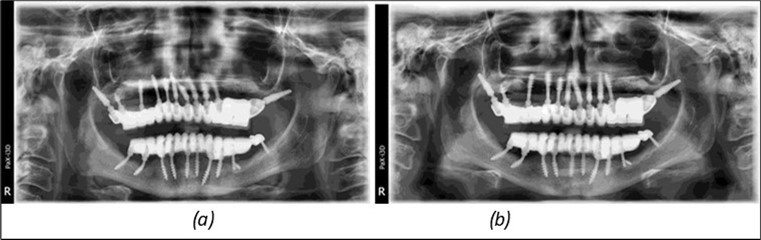

Figure 14.Rx panoramic final situation control: (a) Panoramic X-ray with the addition of a distal BCS implant in quadrant 3 at 11.2022; (b) Control X-ray, 10.2023.

Rx panoramic final situation control: (a) Panoramic X-ray with the addition of a distal BCS implant in quadrant 3 at 11.2022; (b) Control X-ray, 10.2023.

Figure 15.Follow-up panoramic X-ray 09.2025

Follow-up panoramic X-ray 09.2025

The results of rehabilitation treatment with corticobasal and compressive implants with a polished surface after the failure of two stage implants were highlighted over a period of 3 years and 3 months as being very good (Figure 14, Figure 15), with the patient completing a satisfaction survey in this regard. Certainly, it is necessary to continuemonitoring these results in the long term.